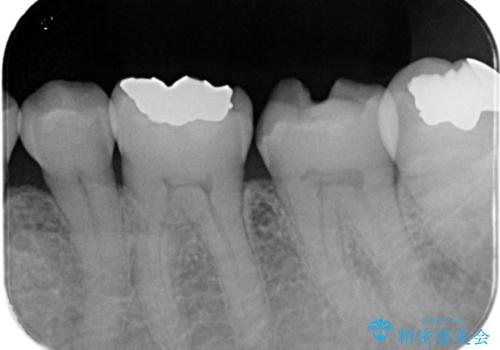

左下7番目の歯の詰め物が外れ、セラミックインレーでのやり替えとなりました。

隣在歯にも保険適用もメタルインレーが入っており、咬合面のインレーと歯質の境目が虫歯になっていたこともあり、合わせてのやり替えとなりました。

左下7番めの歯、フロスを通したらインレーが外れてしまったとのことで、適合具合の精密さや、これを機に白い詰め物にしたいとのことからセラミックインレーでのやり替えとなりました。

また、6番目の歯にも保険適用のメタルインレーが入っており、咬合面インレーと歯質境目にう蝕を認め合わせてのやり替えとなりました。